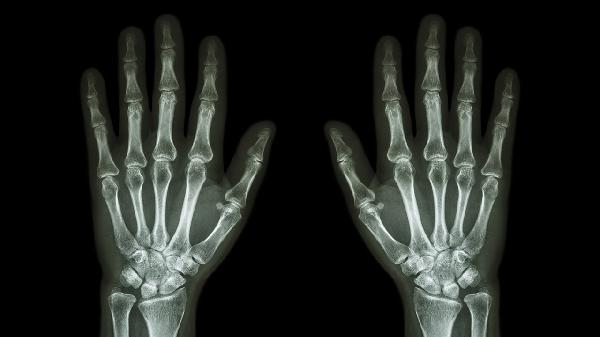

髕骨骨裂怎么快速恢復(fù)

髕骨骨裂可通過制動(dòng)固定、冷熱敷交替、藥物鎮(zhèn)痛、康復(fù)訓(xùn)練、手術(shù)治療等方式促進(jìn)恢復(fù)。髕骨骨裂通常由直接暴力、運(yùn)動(dòng)損傷、骨質(zhì)疏松、慢性勞損、骨骼病變等因素引起。